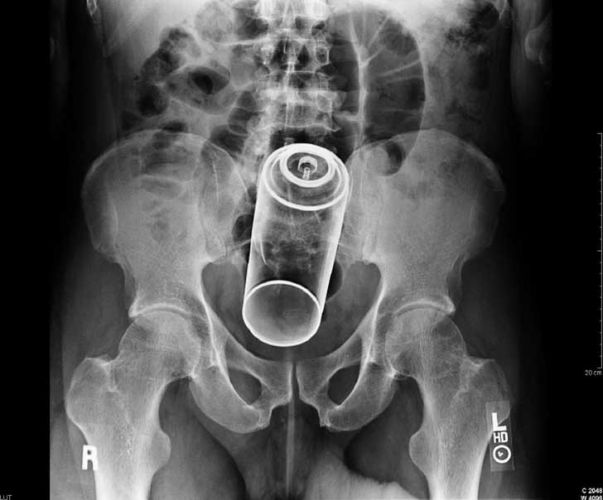

Os objetos mais BIZARROS encontrados no ânus pelos médicos

Lata de Spray